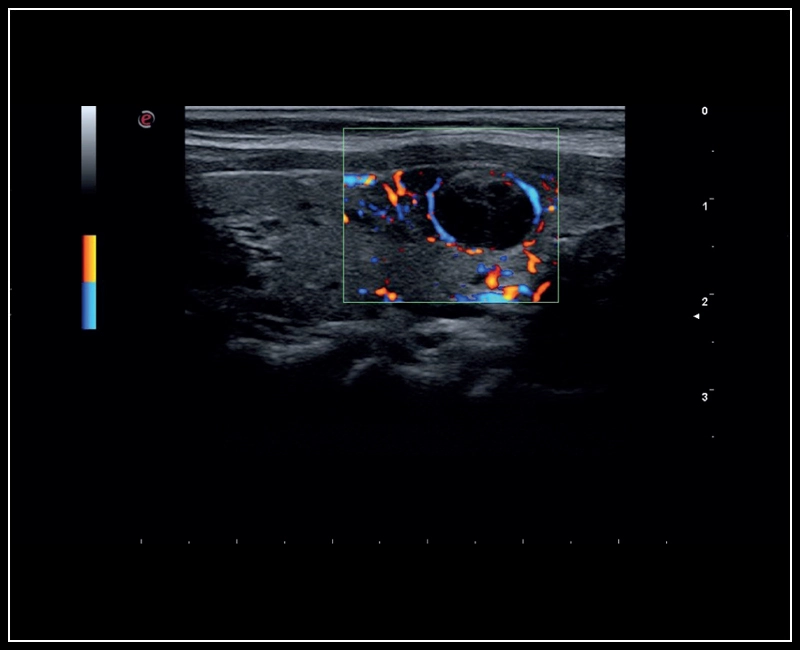

MyLab™9 Platform - XFlow in testis vascularization

MyLab™9 Platform - XFlow in testis vascularization